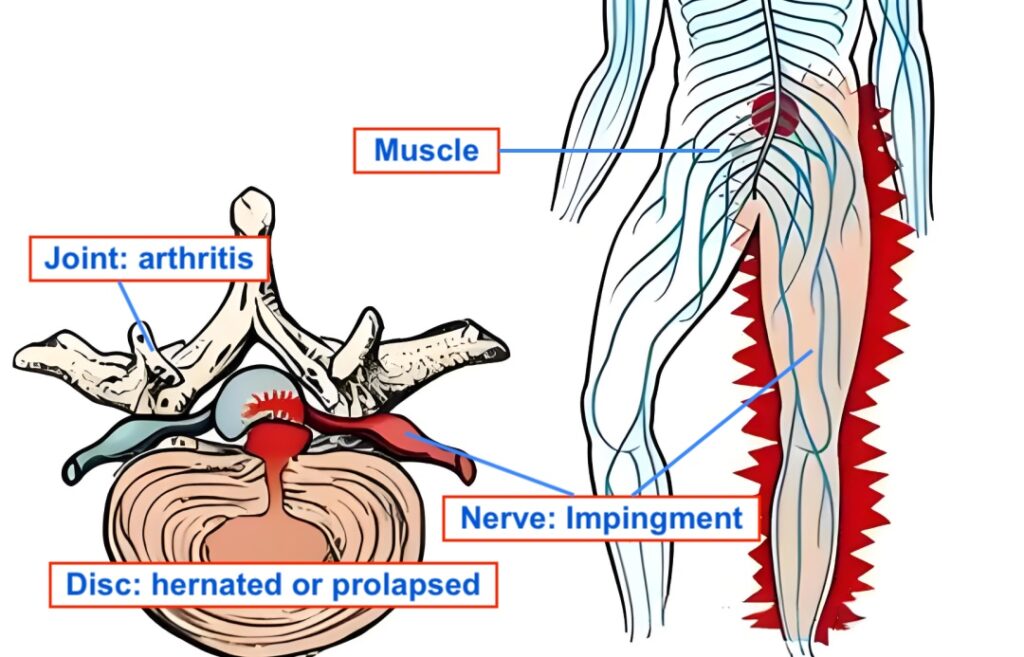

The treatment involves procedures such as:

- Injection of local anaesthetics at the pain site

- Radiofrequency techniques to block nerve pain signals

- Laser technology for targeted pain relief

These methods are performed under imaging guidance like X-ray or ultrasound to ensure accuracy and safety.

“For example, if a slipped disc is pressing on a nerve, interventional pain treatment can target that nerve to reduce the pain signal sent to the brain,” Dr Chen explained.

Patients suffering from conditions such as back pain, knee or hip joint pain, nerve pain, post-surgery pain, cancer-related pain, and chronic headaches may benefit from this approach.

However, Dr Chen cautioned that interventional pain management is not suitable for pain caused by infection, trauma, inflammation, or certain severe nerve conditions.